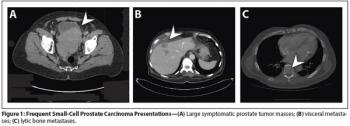

Treatment-emergent small-cell/neuroendocrine prostate cancer is likely to become of increasing clinical relevance in the era of widespread use of potent androgen receptor–targeted therapies.

Aggressive variants of prostate cancer often take the form of neuroendocrine or small-cell carcinomas, which frequently lack androgen receptor expression and respond poorly to hormonal therapies.